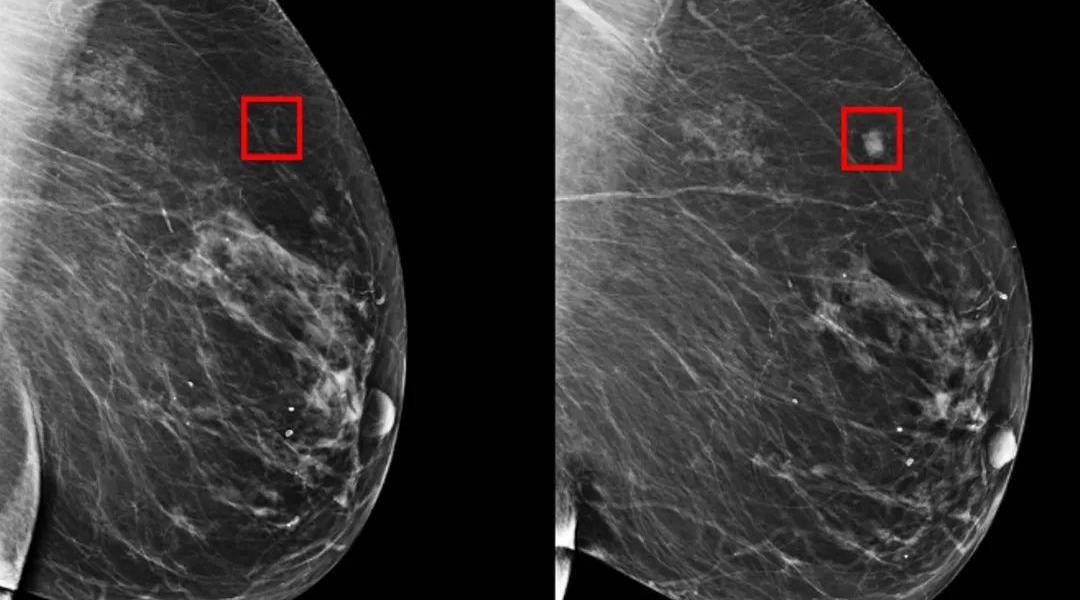

El sistema, que se vale de inteligencia artificial, detectaría ciertos patrones sutiles que no pueden ser identificados por humanos en los tejidos mamarios. Por ello, sería capaz de prever las posibilidades de desarrollar cáncer.

El 31% de los casos de pacientes de alto riesgo fueron predecidos por la IA, representando así una mejora significativa en lo que a prevención del cáncer se refiere. Con las técnicas antes aplicadas, solo se podía predecir el 18% de los casos.